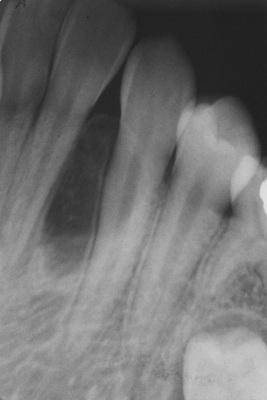

Radiographic Features

- well-circumscribed radiolucent area

- located laterally to roots of vital teeth

- less than 1.0 cm

Radiolucent lesion located lateral to the roots of a vital mandibular canine and first premolar.

lateral periodontal cyst

A larger lesion located lateral to the roots of two vital teeth, causing root divergence.